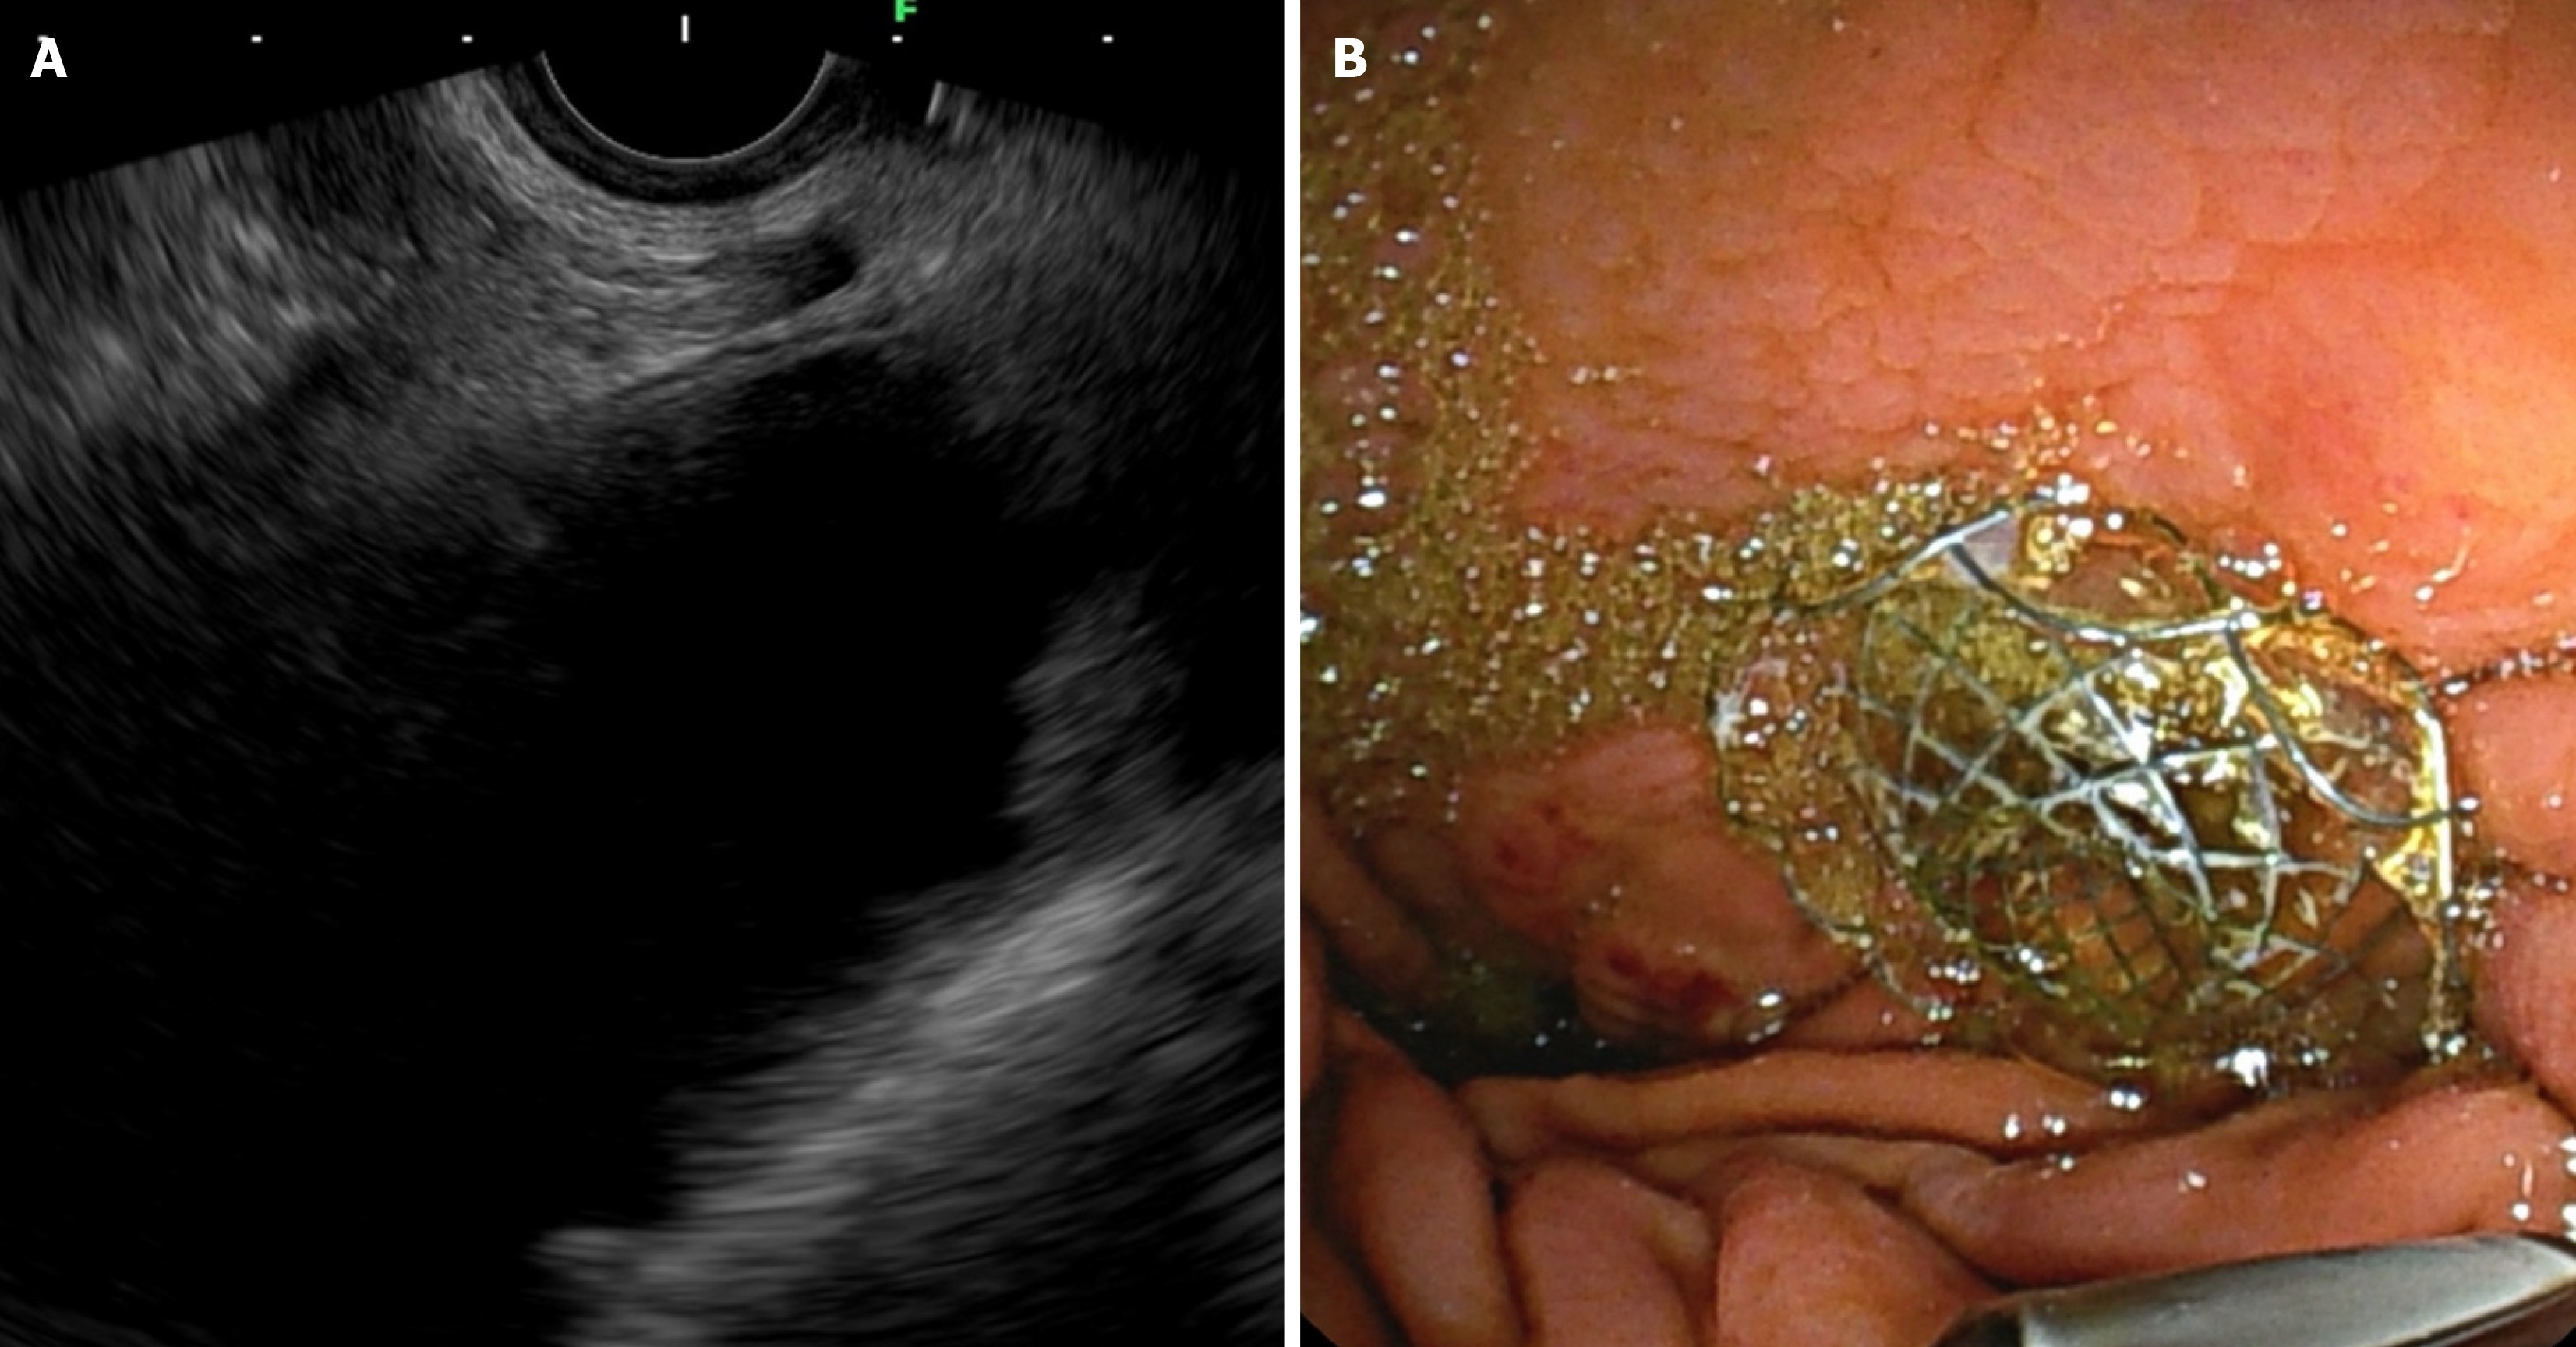

Figure 1 Endoscopic ultrasound-guided gastroenterostomy in afferent loop syndrome.

А: Echoendoscopic view demonstrating the afferent loop; В: Fluoroscopic view confirming the positioning and deployment of the stent.